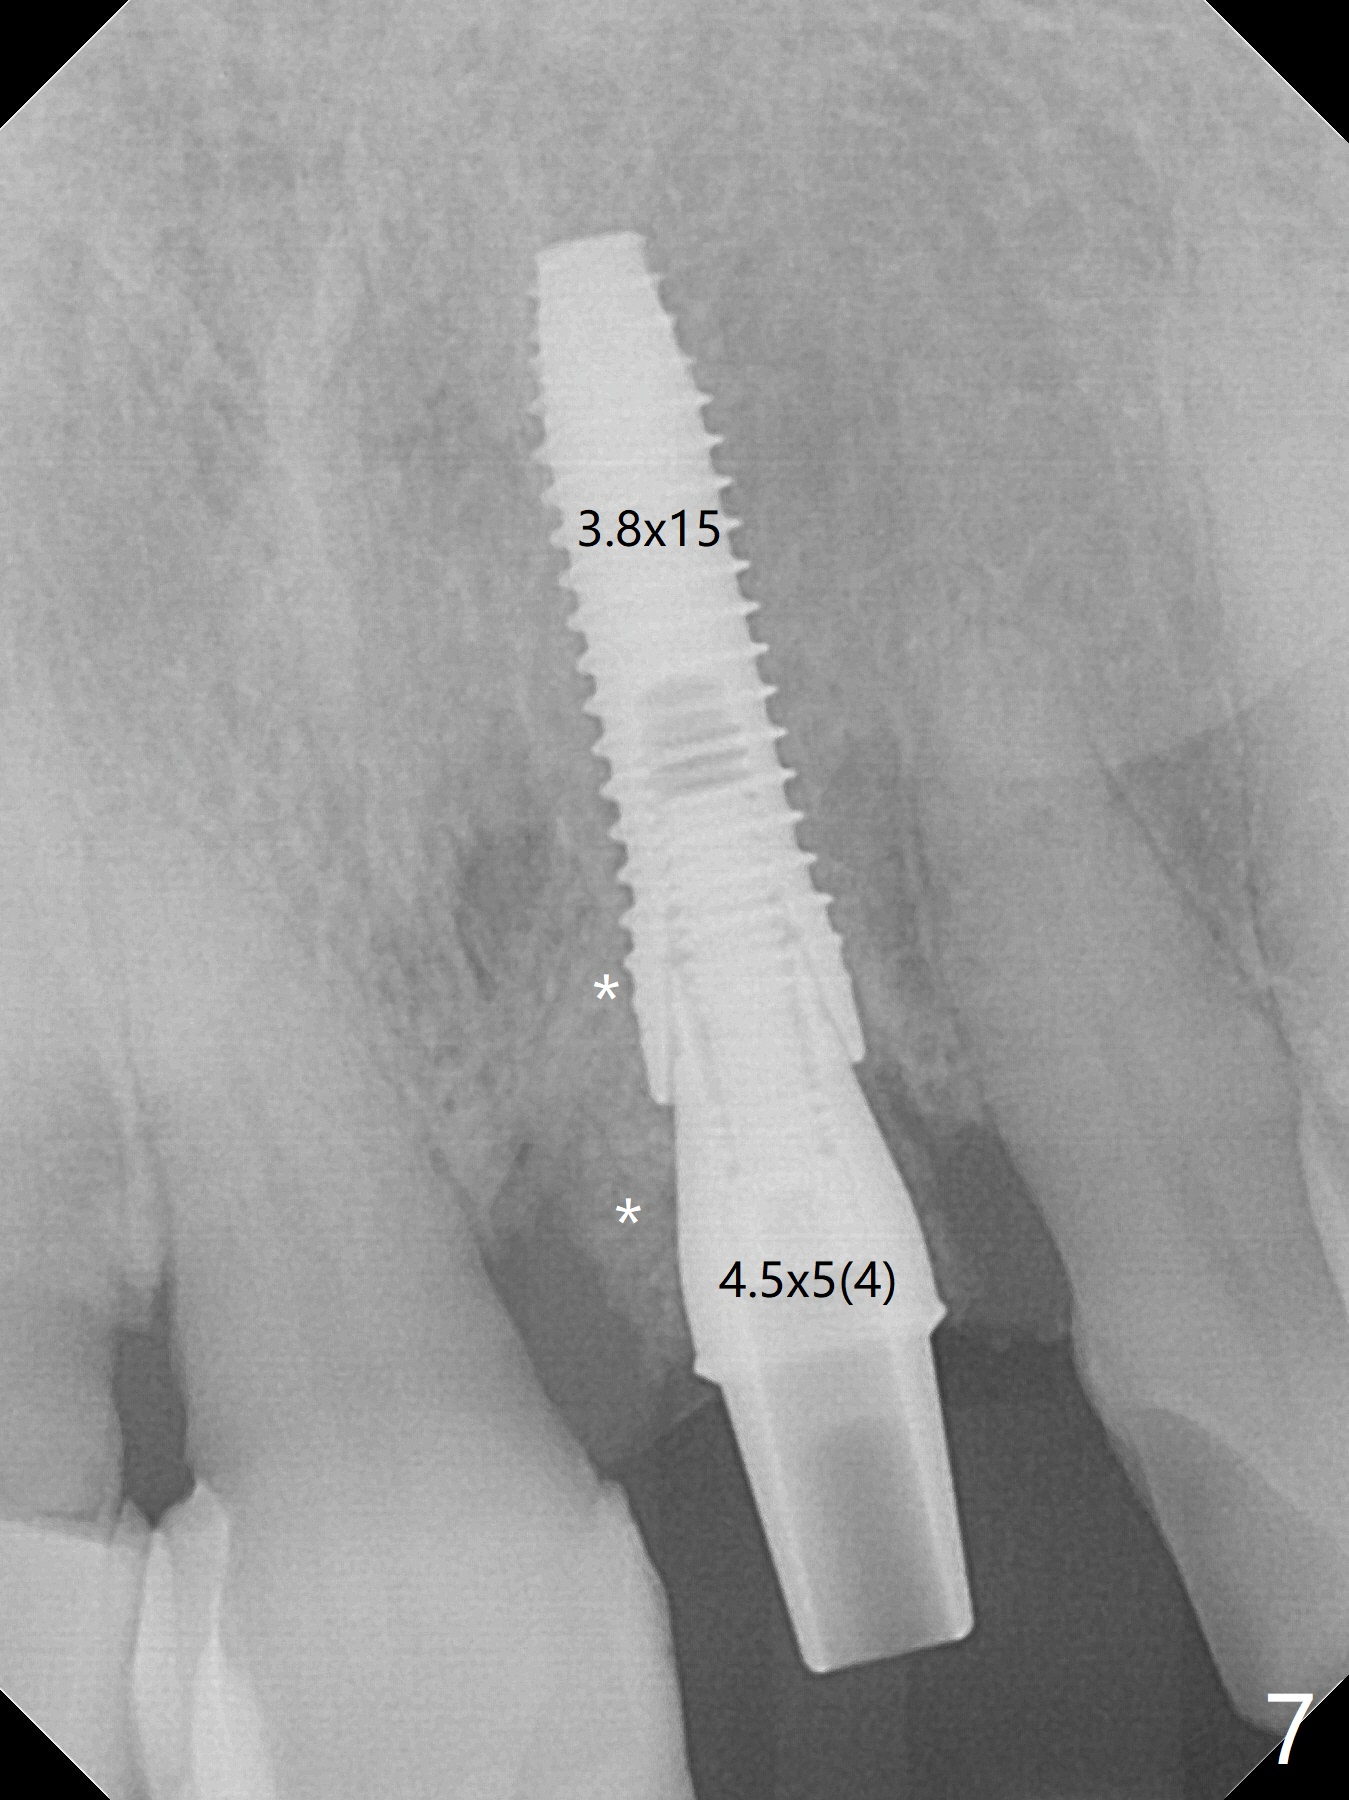

In spite of the incisobuccal shift of the tooth #9 with gingival recession (Fig.1) and loss of the buccal plate (intraop finding), there is no buccal contour collapse (Fig.2 *), due to the presence of the buccal bone of the neighboring teeth and the root of the affected tooth. After extraction, osteotomy (Fig.3) and dummy implant try in (Fig.4), a definitive implant is placed palatally with the buccal gap (Fig.5 *). In fact there is mild buccal contour collapse prior to bone graft (Fig.5 arrow). When allograft (Vera, Fig.6,7 *) is packed buccal to the implant and overlying abutment as a solid support, the buccal contour seemingly returns normal (Fig.6 arrowhead). An immediate provisional is fabricated to prevent loss of the bone graft during healing period. Bone graft kept in place by the provisional turns yellow 6 days postop (Fig.8). The buccal plate remains strong, while the fistula becomes indistinguishable. After adjustment of the provisional margin a few times (nearly 3 months postop, Fig.9,10), the gingival margin appears to have grown incisally, as compared to Fig.1. There is minimal buccal bone collapse (Fig.10). Dislodgement of the abutment and provisional forces her to return 1 year 4 months postop; the socket has healed (Fig.11). The buccal plate is not concave 1 year 4 months postop (Fig.12). The gingiva is slightly recessive (Fig.13) with mild buccal plate concavity (Fig.14) immediately before cementation. The implant could be placed ~ 1 mm deeper (Fig.15).